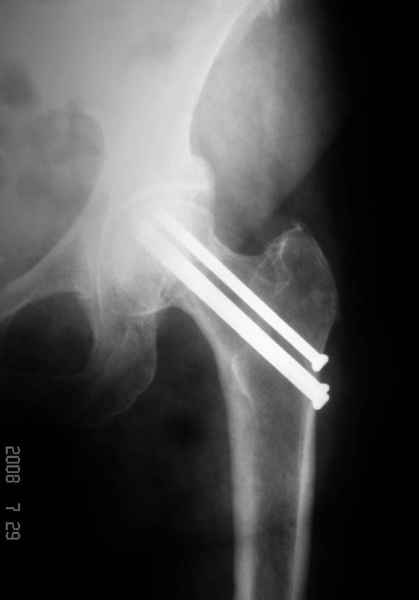

77 летняя больная направлена в нашу клинику на дальнейшее лечение. Из истории, травму получила в сентябре 2007 года и по поводу перелома шейки бедра больная была проперирована тремя каннюлированными шурупами с явным нарушением технологии установки шурупов. Внизу вместо одного шурупа имеется два, что привело к стрессу латерального кортекса. Через месяц по поводу ятрогенного подвертельного перелома сделана фиксация длинной Гамма 3. Установлен без проксимальной блокировки? (set screw). В данный момент имеется несостоятельность конструкции и ложный сустав. Передвигается с помошью костылей, конечность укорочена на 2 см. Какие будут рекомендации?Djoldas Kuldjanov, MDDepartment of Orthopedic SurgerySt. Louis University Medical Center

Михаил, здравствуйте. Если присмотреться - на четвертом снимке есть перелом гвоздя по отверстию.

Видимо, проблем тут две: во-1-х, центральный отломок был оставлен в варусно-сгибательной установке, во-2-х, не динамизировали вовремя.

Нижние винты хотели сломаться, но, увы, один не сломался, и тогда сломался гвоздь. Хотя и при динамизации в таком положении отломков

могло не срастись.